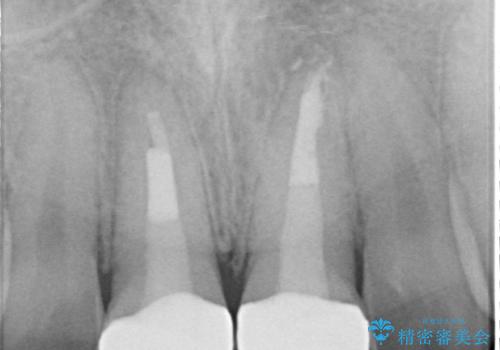

上の前歯は、小さいころにぶつけて折ったとのことで、神経が死んでおり、根の治療が必要な状態でした。

左上の前歯は神経が死んでおり治療が必要な状態でした。また、右上の前歯も根の先に感染がありましたので治療を行いました。